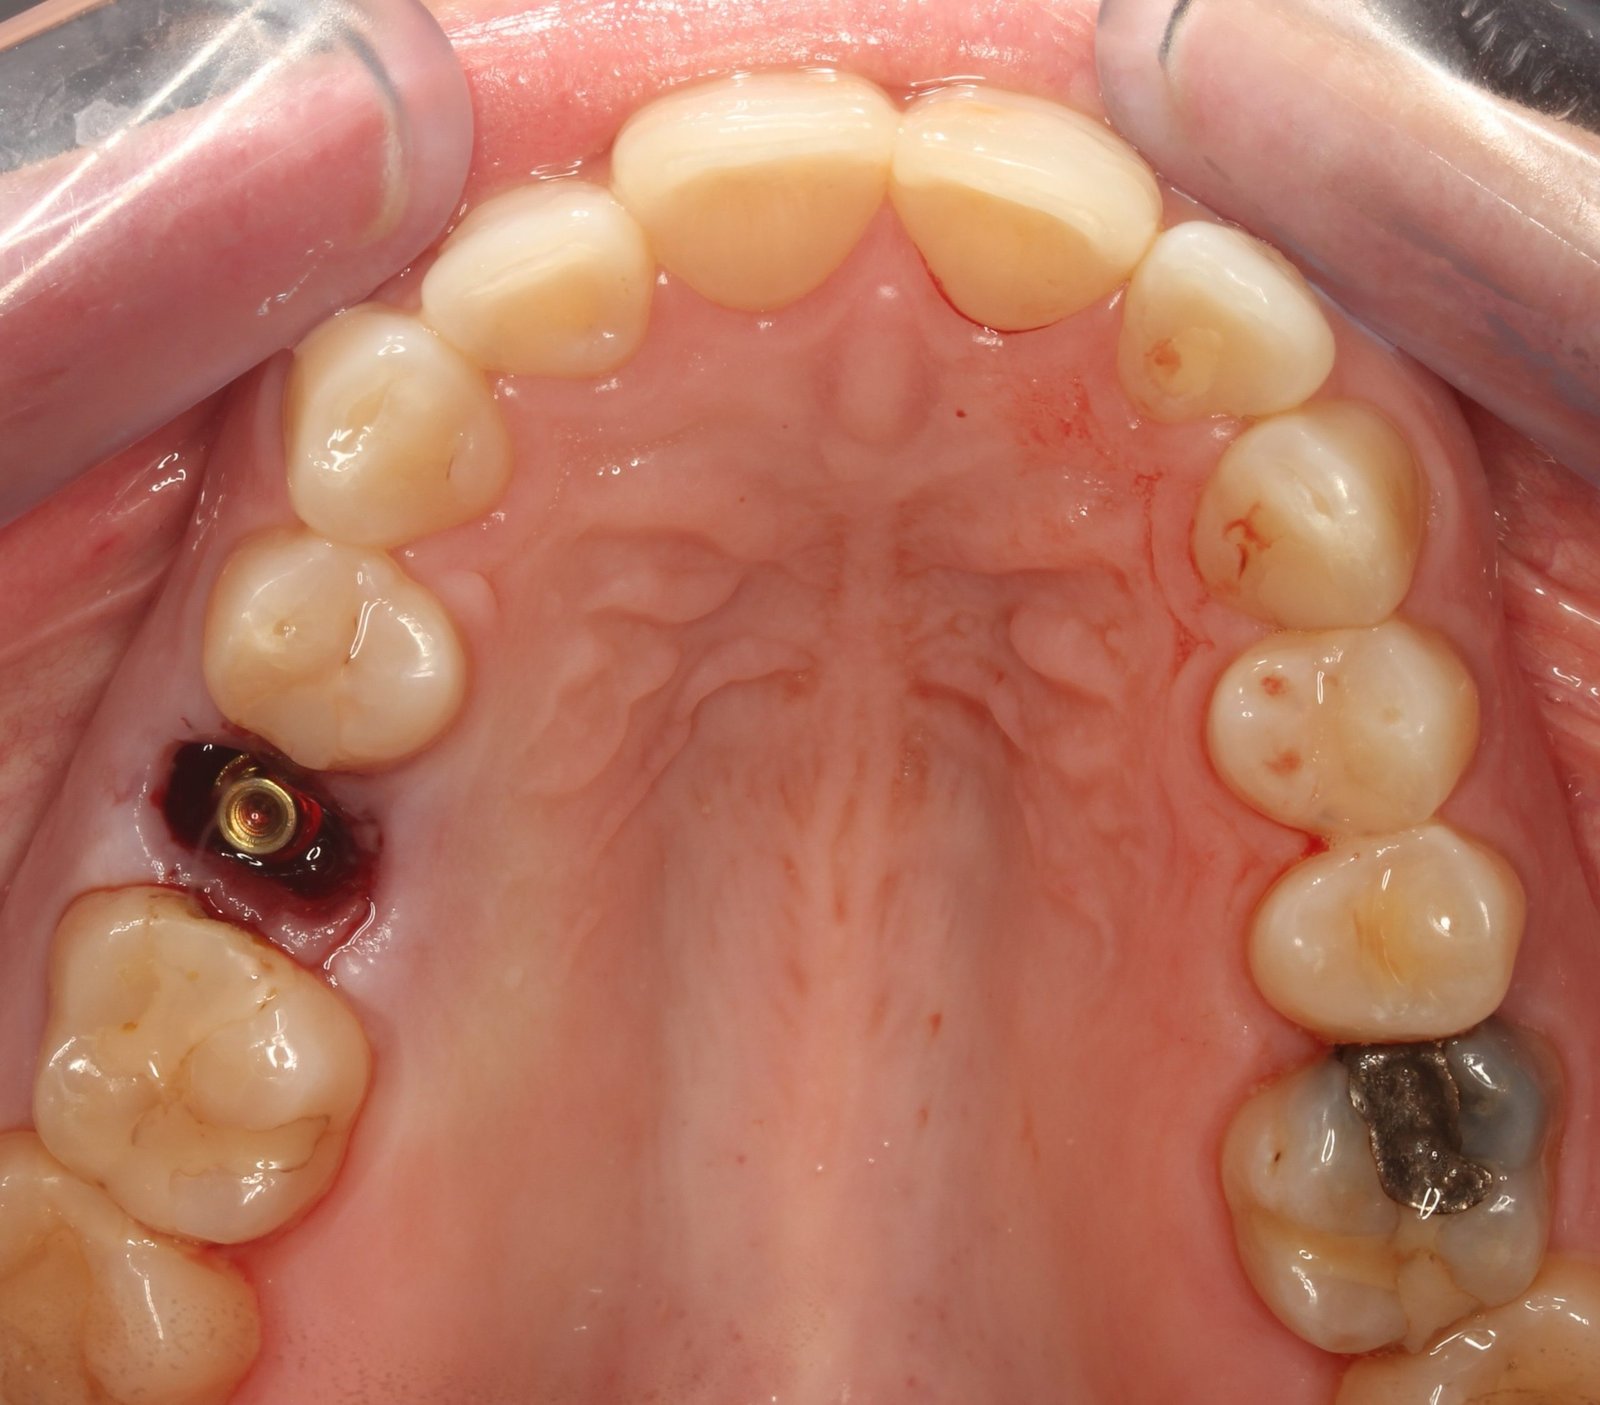

Cirugía Guiada por Ordenador

En nuestra clínica, ofrecemos cirugía guiada utilizando software 3D exacto, una técnica innovadora que nos permite planificar con precisión la colocación de los implantes y asegurar su correcta integración en el hueso maxilar o mandibular. De esta manera, podemos garantizar una colocación precisa, sin errores y con un mínimo de molestias para el paciente.

Durante la cirugía, se utilizan guías quirúrgicas personalizadas basadas en esta planificación digital. Estas guías ayudan a posicionar el implante en el lugar exacto determinado en la planificación, asegurando que esté perfectamente alineado y rodeado de suficiente hueso, lo cual es crucial para su integración y estabilidad a largo plazo. Además, esta precisión garantiza que el implante esté en la posición óptima para recibir la prótesis dental, lo que mejora la funcionalidad y estética del resultado final.